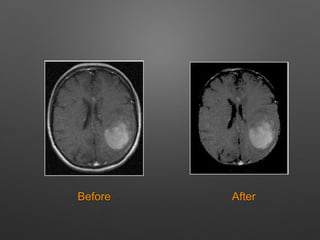

Before After

Skull Stripping • Skullstripping is an important process in biomedical analysis and it is required for the effective examination of brain tumour from the MR images. • It is the process of eliminating all non-brain tissues in brain images.